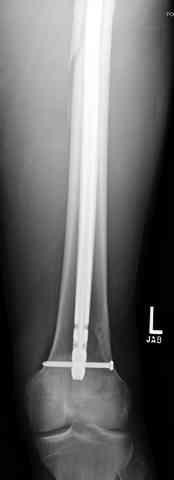

Здесь представлены несколько случаев лечения огнестрельного перелома

1 Проксимальный перелом бедра, антеградный гвоздь